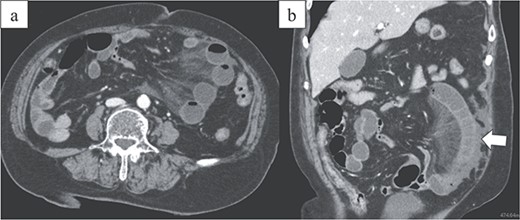

An 86-year-old woman with no prior abdominal surgeries was admitted to our hospital complaining of constant abdominal pain with an acute onset of 8 hr duration. The physical examination revealed tenderness of the lower abdomen. The laboratory test results were unremarkable, except for elevated lactate (3.0 mmol/l) and leukocyte counts (14 400/μl). Contrast-enhanced computed tomography (CT) revealed a closed-loop obstruction of the hypo-enhancing small bowel in the left lower abdominal quadrant, which suggested a strangulated bowel obstruction (Fig. 1). The duodenum did not form a horizontal limb and ran caudally to the jejunum (Fig. 2). The duodenojejunal flexure was abnormally located in the right upper abdominal quadrant, which suggested an intestinal malrotation. Sac-like capsulated small-bowel loops were barely visible.

Image from enhanced CT. Contrast-enhanced CT shows the absence of a horizontal duodenal leg and the duodenum running caudally to the jejunum (arrowhead).